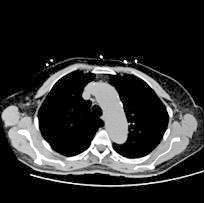

Se revisaron las pruebas solicitadas en Urgencias. En la analítica se en contró una hemoglobina (Hb) de 14 g/dl, un volumen corpuscular medio (VCM) elevado (106μ³) compatible con su historia de alcoholismo o con un déficit de ácido fólico o vitamina B12, una discreta elevación de la proteina C reactiva (13,2 mg/dl) sin elevación de otros reactantes de fase aguda y unas enzimas hepáticas dentro de la normalidad, con la aspartato transfe rasa ligeramente elevada 39 U/L (rango de normalidad: 5-34). Los tóxicos en orina fueron negativos, así como la etanolemia. La radiografía (rx) de tórax mostraba una condensación en el lóbulo superior izquierdo en posi ble relación con la infección tuberculosa diagnosticada en 2011 (Figura 1). La TC -a pesar de no mostrar signos de patología aguda intracraneal, ni masas ni signos de sangrado- sí que mostraba atrofia cerebral con surcos muy marcados, hallazgo no concordante con la edad de nuestro paciente (Imagen 2).

Figura 2.

TC craneal corte transversal. Aumento de la profundidad de los surcos en posible relación a signos de atrofia encefálica acentuada para la edad del paciente sin que se observen claras lesiones focales ni colecciones o signos de sangrado intra o extraaxial. Se observa una tenue hipodensidad del esplenio del cuerpo calloso.